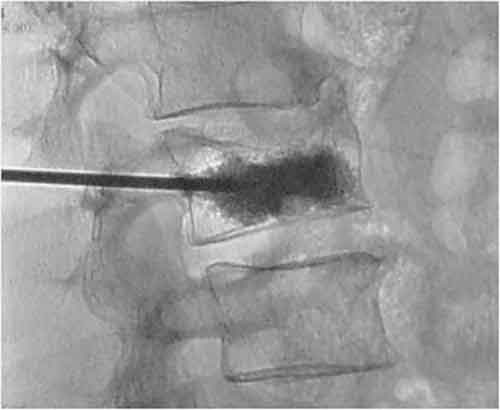

“La terapia delle fratture vertebrali da cedimento su base osteoporotica, prevede la prescrizione di lunghi periodi di immobilità forzata a letto, l’uso del busto ortopedico per diversi mesi e una massiccia assunzione di farmaci per lenire l’intenso dolore alla schiena – spiega Chioffi. Con l’introduzione della procedura chirurgica “cifoplastica con palloncino”, si ottiene un’immediata regressione del dolore e si consente una rapida mobilizzazione del paziente. Si tratta di un intervento chirurgico rapido e mininvasivo della durata di circa mezz’ora, eseguibile, salvo casi particolari, in anestesia locale, con dimissione in giornata. Questa tecnica prevede una prima fase di inserimento e gonfiaggio temporaneo di un palloncino all’interno della vertebra fratturata, sempre attraverso un accesso percutaneo sotto controllo radiologico con il quale si ottiene una riespansi one del corpo vertebrale, e successivamente vi si introduce del cemento con per ottenere un immediato rinforzo della vertebra lesionata.

L’equipe del Dottor Chioffi ha eseguito negli ultimi anni numerosi trattamenti mininvasivi di cifoplastica con palloncino.Sono stati trattati sia pazienti affetti da crolli singoli sia multipli del tratto dorsale e lombare della colonna vertebrale. I buoni risultati ottenuti confermano l’efficacia di questa tecnica.